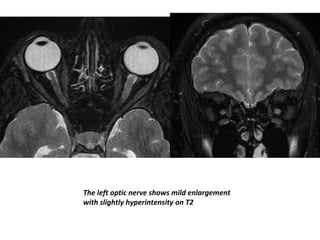

The left optic nerve shows mild enlargement

with slightly hyperintensity on T2

The left opticnerve shows mild enlargement with slightly hyperintensity on T2

The left opticnerve shows mild enlargement with mild post contrast enhancement on T1.